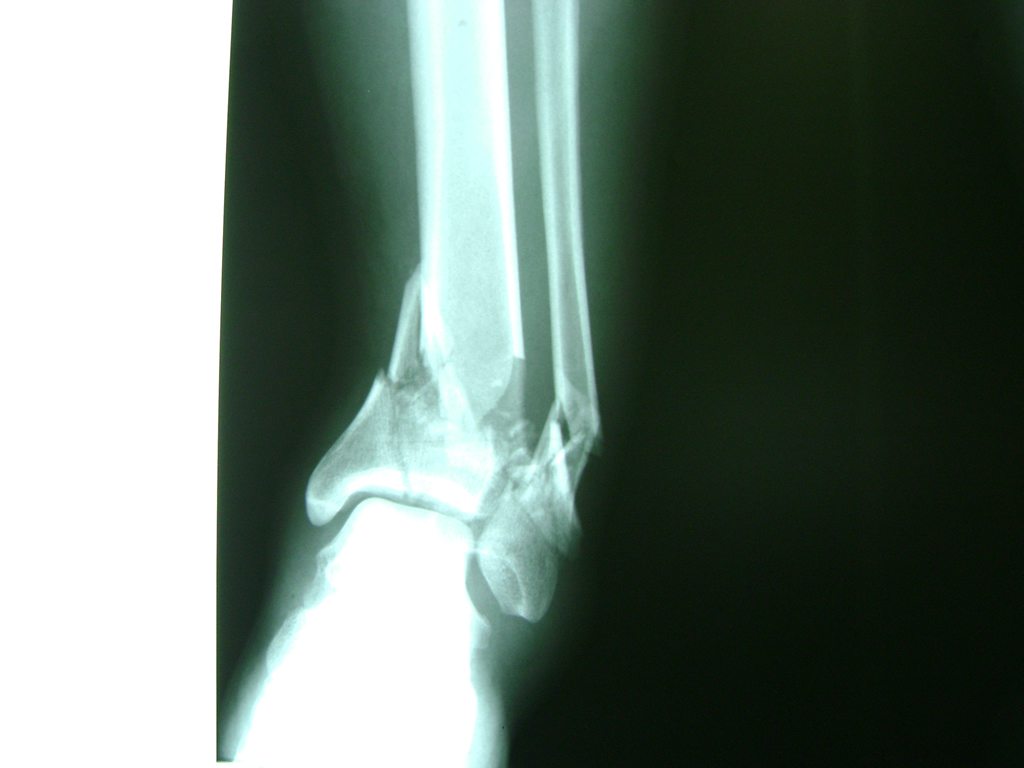

Una fractura de tobillo es la rotura de uno o más de los huesos del tobillo. Estas fracturas pueden ser:

- Producirse en uno o ambos lados del tobillo.

- La fractura se extiende hasta la articulación del tobillo (fractura intra-articular).